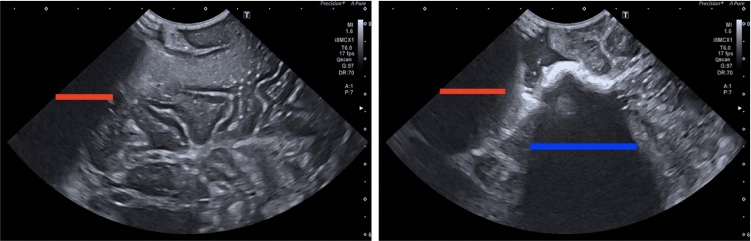

Purpose: Intraoperative ultrasound scanning is a demanding visuotactile task. It requires operators to simultaneously localise the ultrasound perspective and manually perform slight adjustments to the pose of the probe, making sure not to apply excessive force or breaking contact with the tissue, while also characterising the visible tissue.

Method: To analyse the probe-tissue contact, an iterative filtering and topological method is proposed to identify the underlying visible tissue, which can be used to detect acoustic shadow and construct confidence maps of perceptual salience.